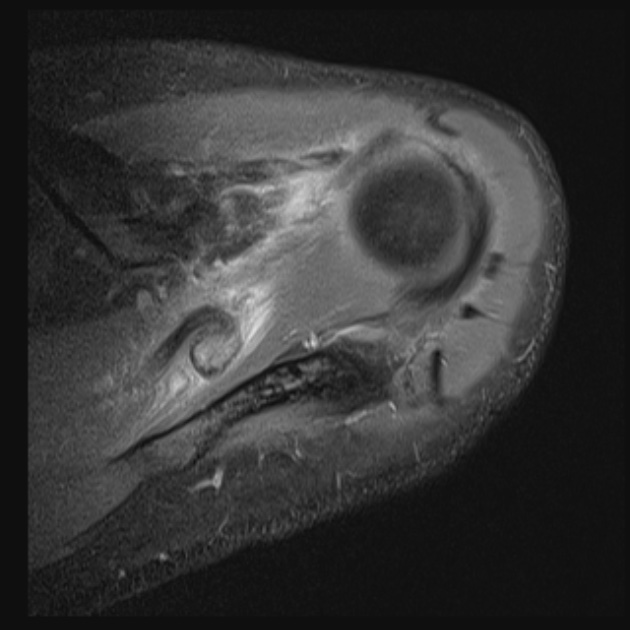

The surgeon said the tear wasnt visible from the articular side and debridement was necessary to reach it from the bursa. The tendon was stuck down and a side to side repair was necessary. You can make out the central defect in the footprint with intact articular and burial surfaces.

I have seen a few of these in Infraspinatus, as per the article linked below, but this was my first in Supraspinatus. Reference article.

Massive interstitial delamination of Supraspinatus with retraction